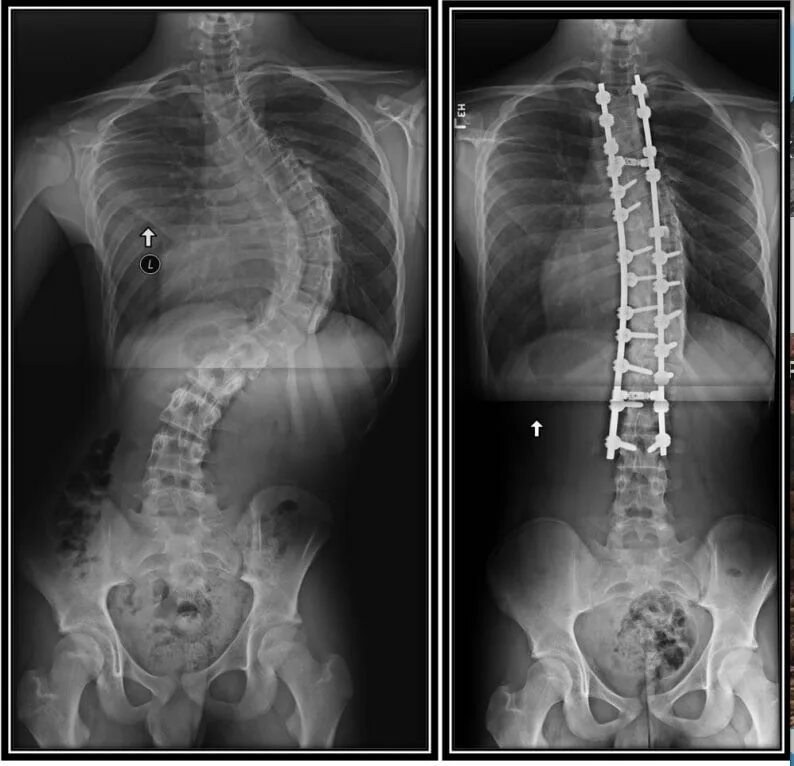

Гипоплазия 12 пары ребер